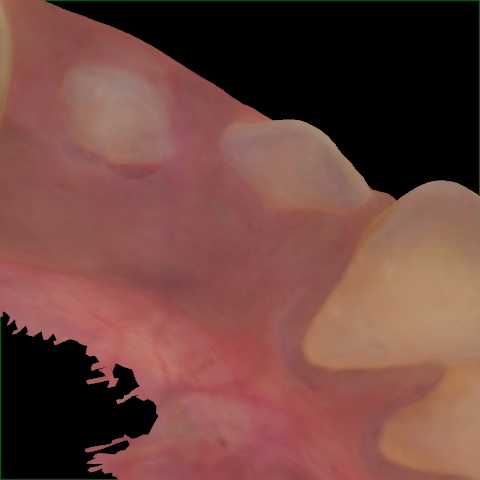

NHD25470

Annotated as "Good"

Original Image Rendering Image